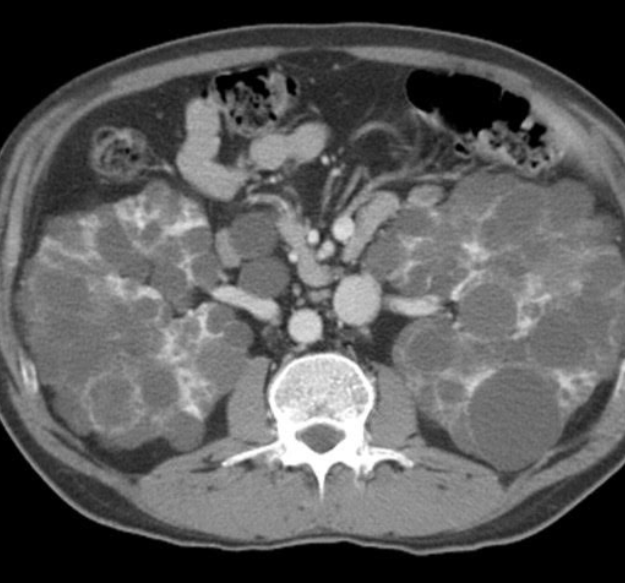

Simple and complex kidney cysts

Kidney cysts result from genetic or non-genetic processes. It can occur and affect children and in adults. It is usually diagnosed when a person goes for an ultrasound scan, CT scan or MRI scan of the abdomen. Kidney cysts can be divided to simple kidney cysts or complex kidney cysts. There is another condition where the kidney is filled with multiple kidney cysts which will be covered under cystic kidney disease.

The most common cause of these cysts are radiologically evident kidney cysts in adults are simple kidney cysts.